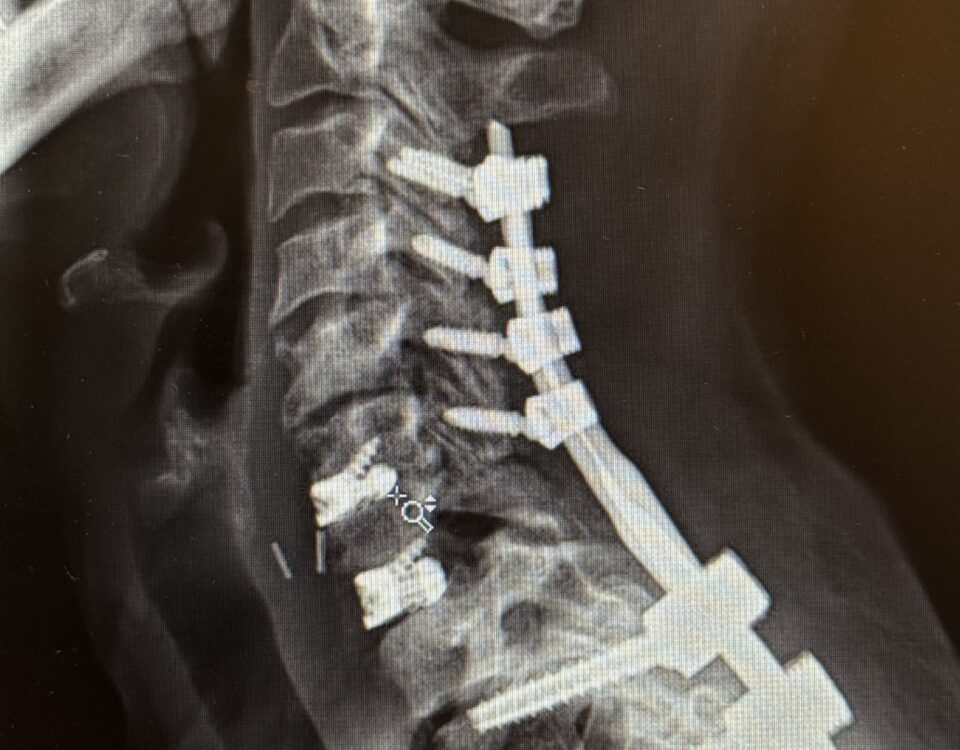

REVISION SURGERY TREATS INTRACTABLE NECK PAIN & CERVICAL DEFORMITY Clinical Presentation The patient is a 61-year-old female with a history of rheumatoid arthritis. She is 2-1/2-years […]